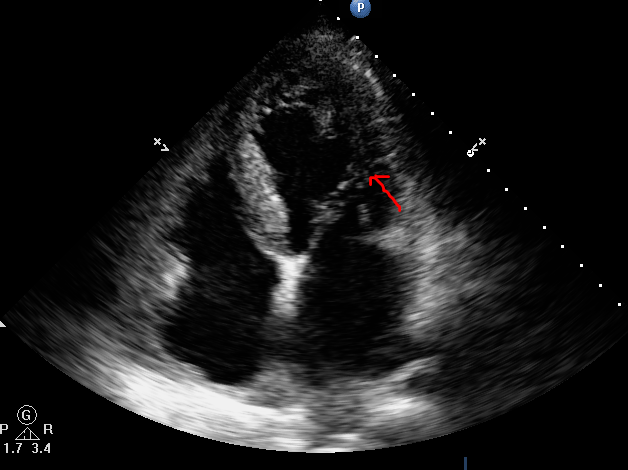

曾经误以为的降落伞样二尖瓣

二尖瓣狭窄的超声心动图诊断以及典型病例分享

降落伞型二尖瓣先天性心脏病超声